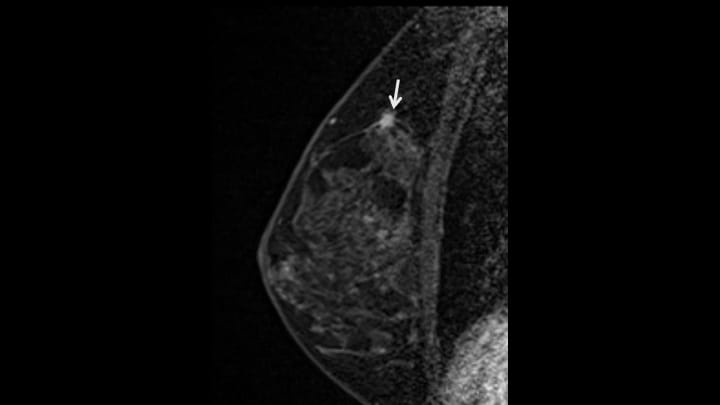

2. T1強調画像(造影前)

左に比較し、右乳腺上部には収縮性の変化(構築の乱れ)が認められる(矢印)。